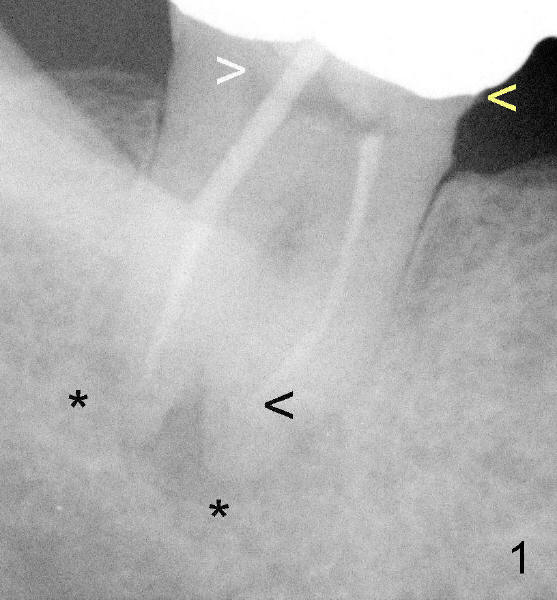

Fig. 1 and 2 show the abutment tooth #32 in vivo and in vitro, respectively. Yellow < in Fig.1,2 point to open margin in the mesiobuccal aspect of the crown/tooth. While the white > in Fig.1 points to unfilled pulpal chamber, the one in Fig.2 shows more clearly the void around the post in the distal canal. Oblique projection shows curved void associated with the mesial canal (Fig.2). RCT failure is complex, both endodontic and restorative (coronal leakage). Return to main text